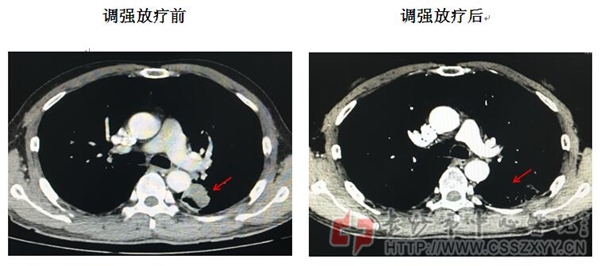

左肺磷癌调强适形放疗效果